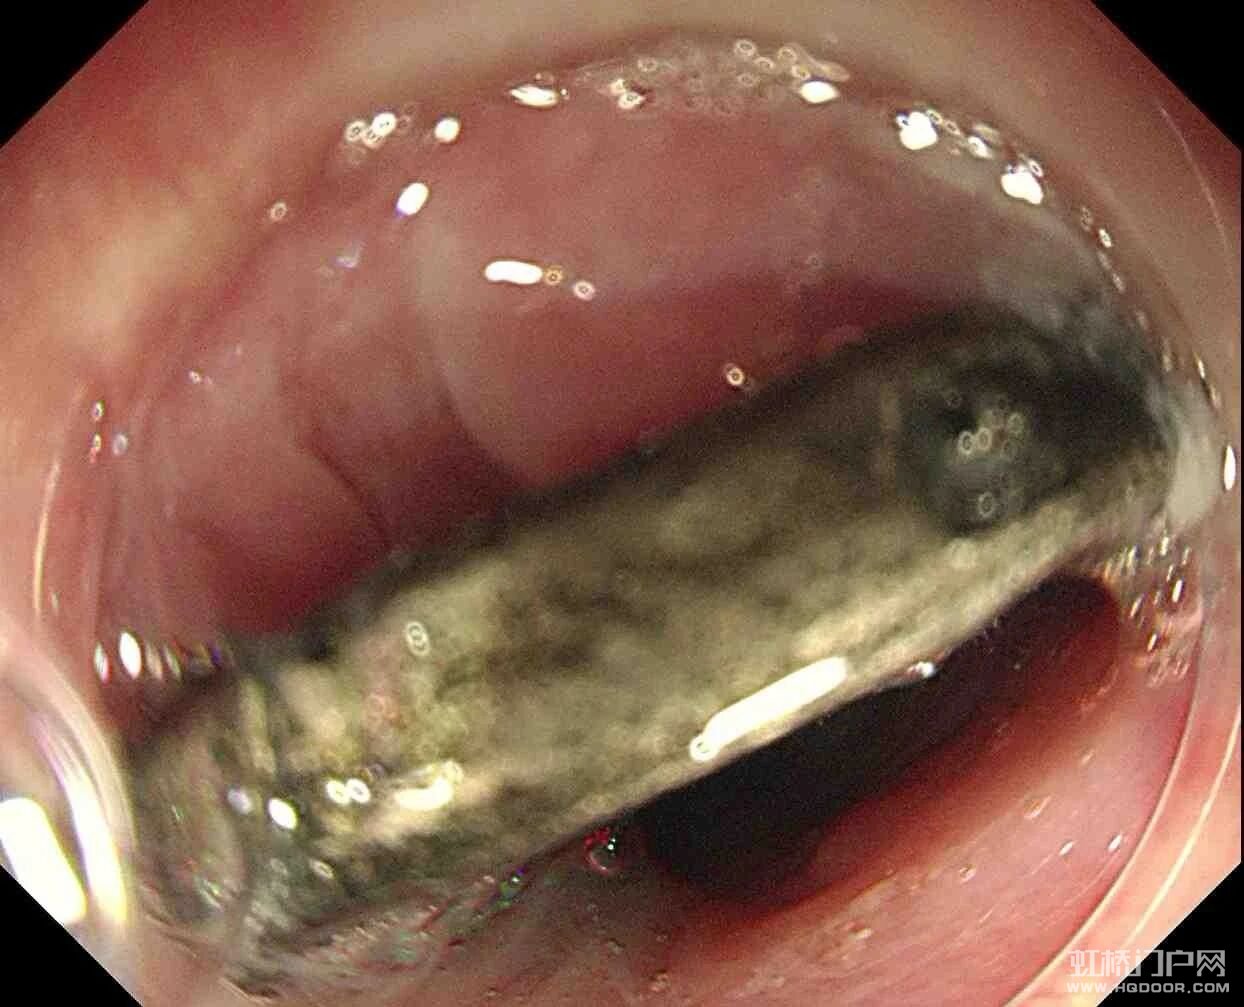

虹桥一名4岁孩子误吞一元硬币,卡在食管长达两个多月,家长一直没察觉。直到孩子频繁喊胸口不舒服,到二医检查才发现。孩子饱胃且异物滞留过久,手术风险极高,好在医院内镜科与麻醉科联手,仅用2分钟就成功取出硬币。真的太惊险了,这么小的小孩家长一定要看好啊